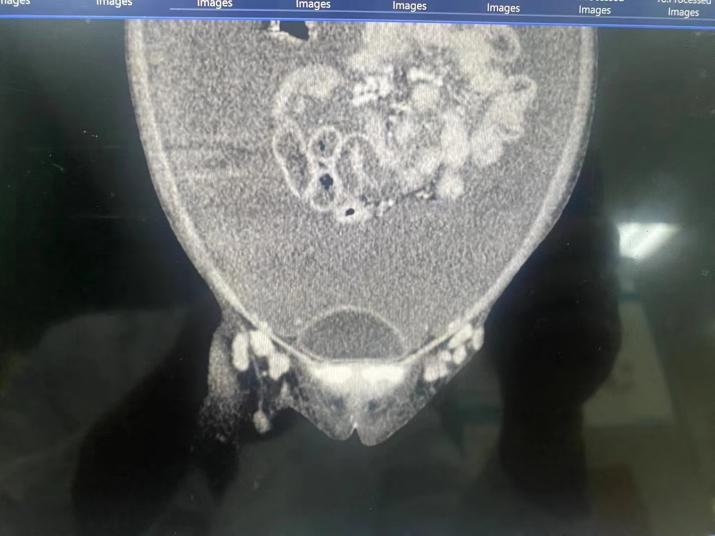

当地医院 B 超结果显示,小月腹腔大量腹水、双侧胸腔中等量积液,情况不乐观。

浅表器官超声检查提示,小月双侧颈部、腋窝、腹股沟淋巴结肿大,其中腋窝淋巴结最大有将近 2 cm。于是,聚焦点在淋巴结病理检查,可是小月已经在外院的淋巴结活检未见异常,经我院病理科会诊也没有明确的诊断。

面对如此棘手的难题,老年消化内科组织多学科会诊。在血液系统疾病诊断中有丰富经验的病理科顾永耀教授、血液内科二病区罗军教授等专家将所有线索整合在一起,结合病史和现有检查结果,抽丝剥茧,关键性证据淋巴结病理结果也终于浮出水面,最终确定了「致病元凶」——浆细胞型 Castleman 病重型。